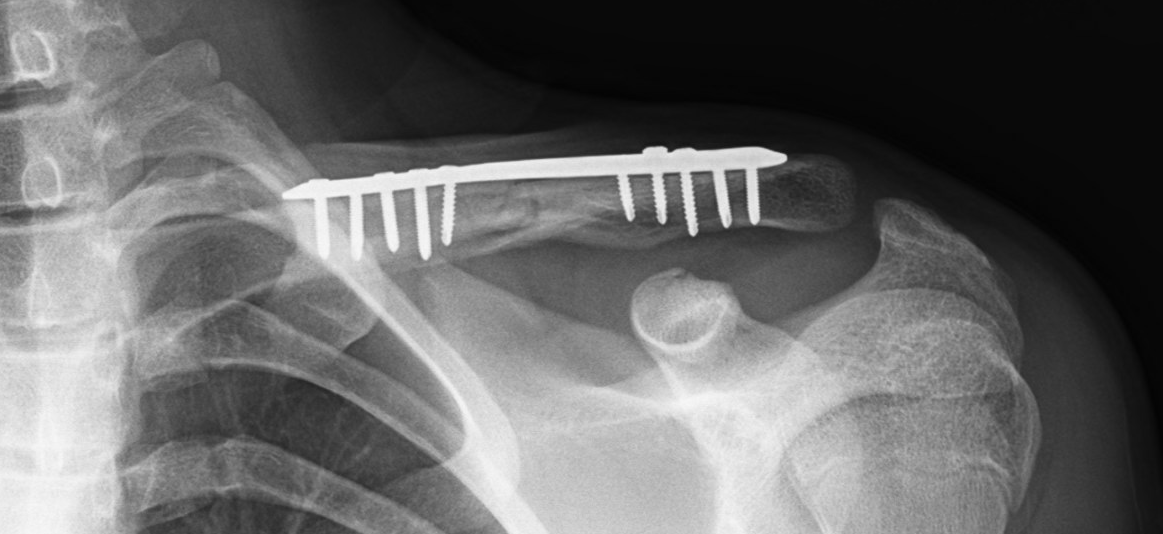

This is a “displaced” clavicle (collarbone) fracture. The fracture is also “shortened” as the ends of the bone are overlapping each other.

Here is the same fracture as above after undergoing surgical treatment. The surgery is called open (make an incision) reduction (line up the bone) internal fixation (generic term for stabilizing the fracture, generally with metal plates and/or screws.